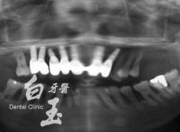

治療後